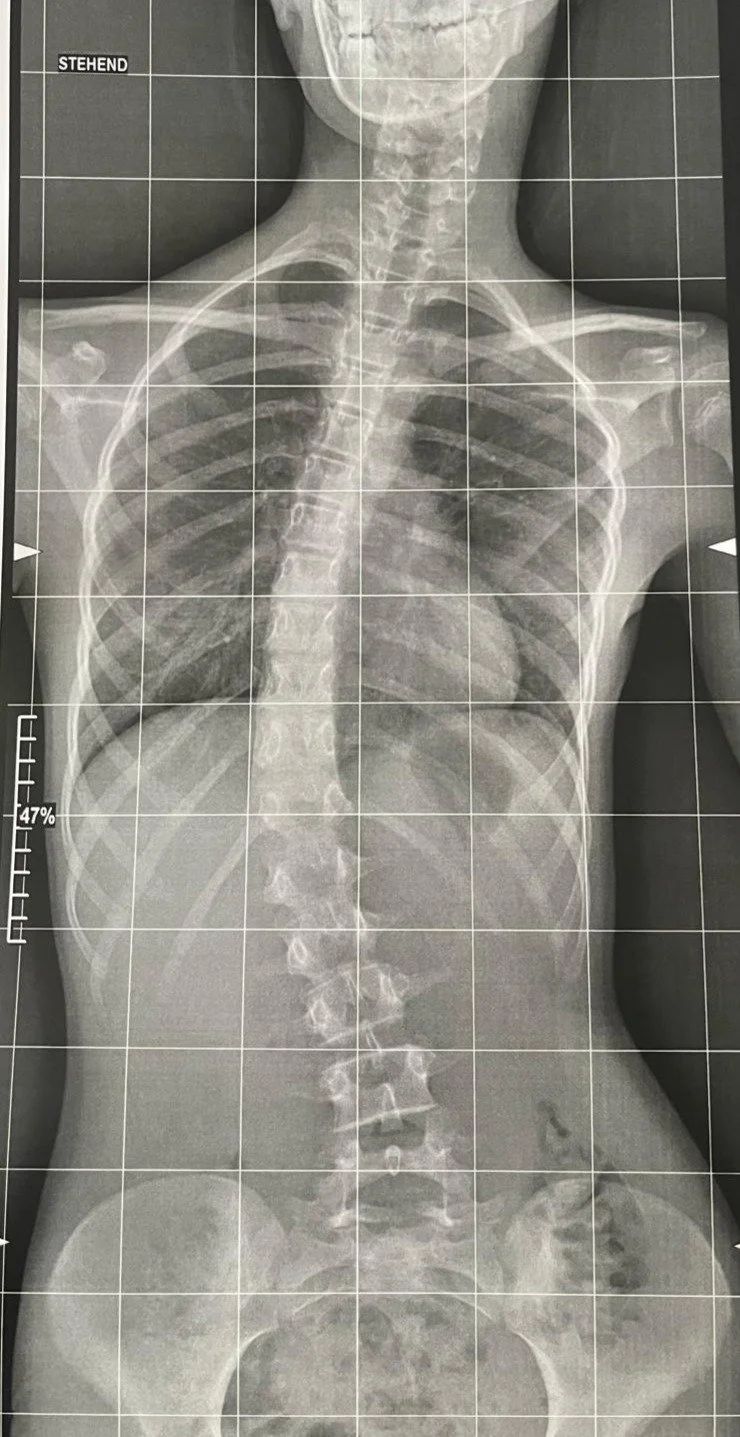

Ausgangssituation und Veränderung nach 3 Behandlungen innerhalb von 5 Wochen. Das zu Beginn der Behandlung angepasste Korsett wurde gleich wieder weggelassen.